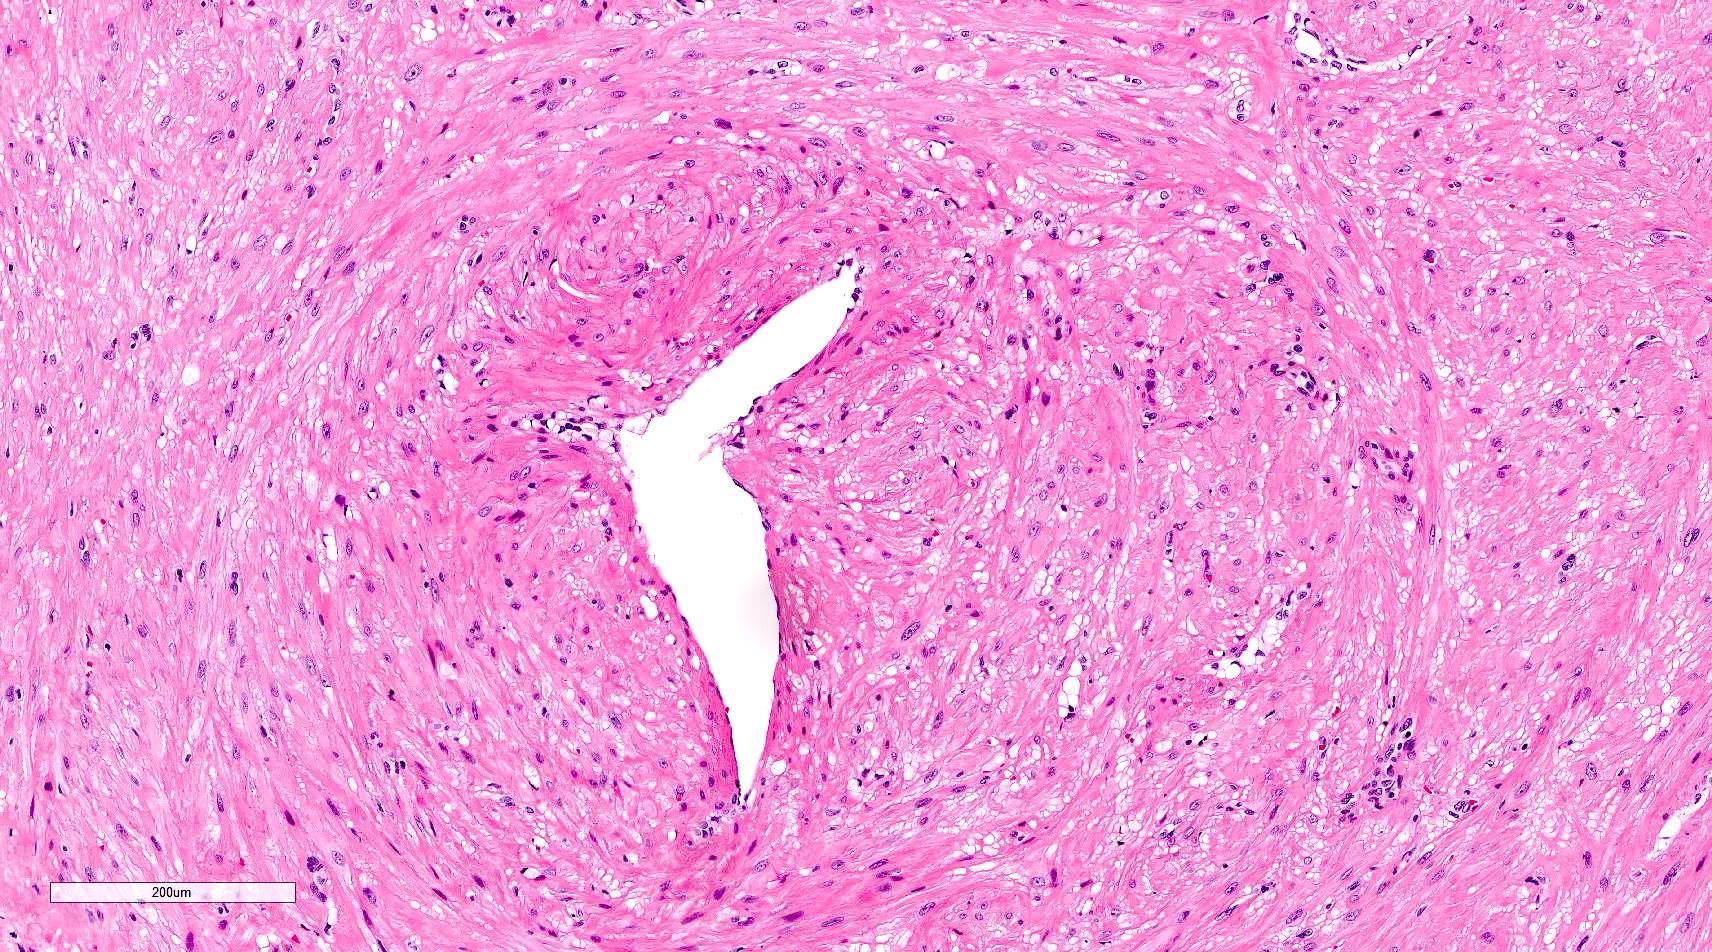

Microscopic (histologic) description

- Encapsulated proliferation of eosinophilic smooth muscle cells with minimal nuclear pleomorphism

- Rounded or slit-like veins with muscular walls present within the tumor (J Cutan Pathol 2017;44:342)

- Tumors can further be classified into 3 subcategories, first described by Morimoto et al:

- Solid type: smooth muscle bundles surround numerous small slit-like channels

- Cavernous type: dilated vascular channels, the walls of which are difficult to distinguish from the intervascular smooth muscle

- Venous type: thick walled vessels that are easily distinguished from the intervascular smooth muscle

Microscopic (histologic) images

Contributed by Ohoud Aljarbou, M.D., Jijgee Munkhdelger, M.D., Ph.D. and Andrey Bychkov, M.D., Ph.D.

A. Angioleiomyoma. A mixture of smooth muscle bundles arranged in small fascicles and intervening vascular channels is noted. The concentric perivascular spindle cell proliferation which is characteristic for myopericytoma is absent. There are no glomus cells seen. Adipocytes are not seen in this image, which makes angiomyolipoma less likely.